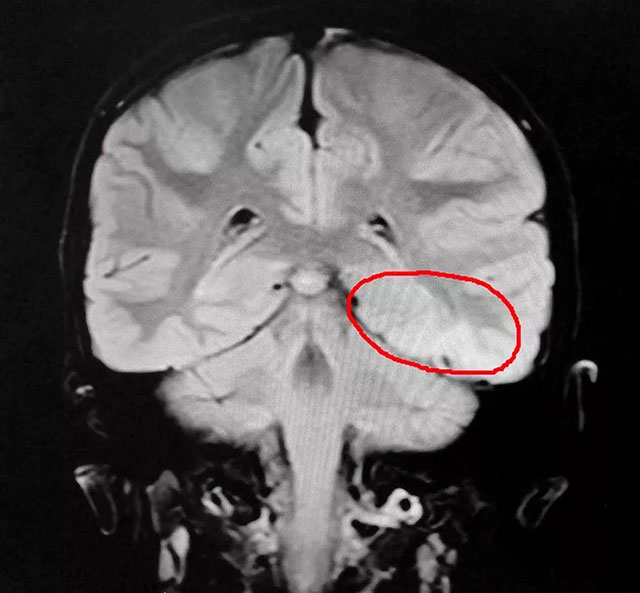

頭顱MR平掃+增強(qiáng)+MRS+MRSI檢查示:左顳葉(皮層區(qū)近小腦幕)病變,增強(qiáng)后未見明顯強(qiáng)化,結(jié)合MRS,考慮良性病變,結(jié)合腦電、磁共振等多項檢查終于在龍龍的大腦中確定了致癇區(qū)。

▲ 患兒癲癇病灶區(qū)域

楊忠旭教授指出,患者癲癇診斷明確,經(jīng)系統(tǒng)藥物治療無任何改善,確診為難治性癲癇,應(yīng)用現(xiàn)代神經(jīng)影像學(xué)技術(shù)和電生理監(jiān)測技術(shù),能明確引起癲癇發(fā)作的“責(zé)任病變”,手術(shù)指征明顯,未見明顯手術(shù)禁忌癥。楊教授為患者制定了周全的手術(shù)方案并做好充分準(zhǔn)備,準(zhǔn)備行“癲癇病灶切除術(shù)”。